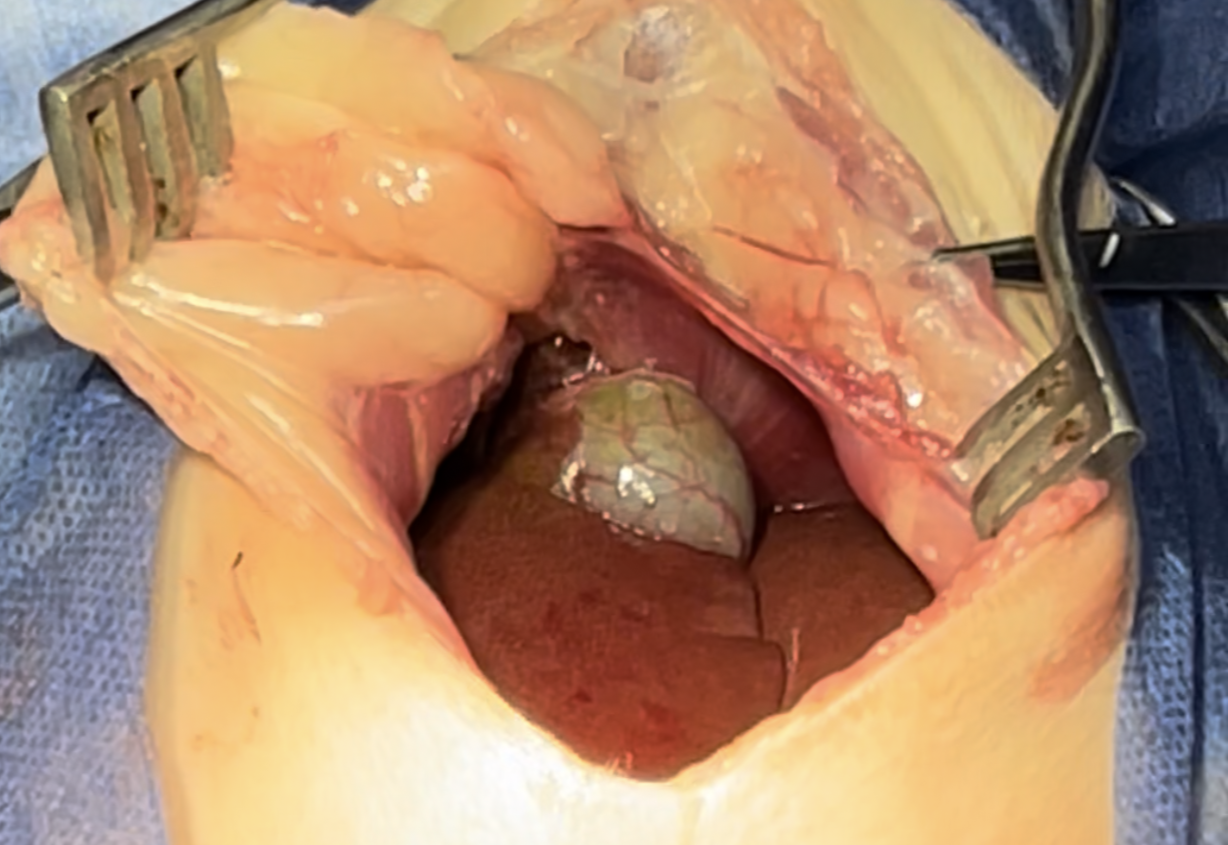

intestines & Liver lobe passing through a narrow hole after being healed over

Widening the herniation to allow organ exteriorization